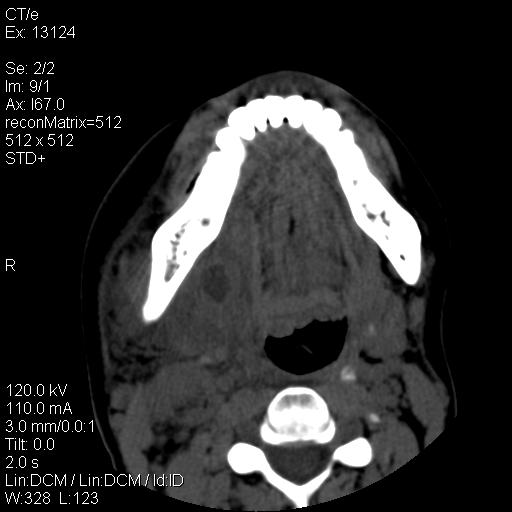

标题: CT18257:女,29岁,右下磨牙痛 [打印本页]

标题: CT18257:女,29岁,右下磨牙痛

女,29岁,右下磨牙痛,因产后2月,故未治疗。现右颌肿痛伴张口困难。请大家看看右侧鼻咽部、口咽部是否

1.考虑右侧下颌区脓肿(牙源性)

考虑右下智齿冠周炎伴周围软组织炎症,脓肿形成

1)考虑右侧下颌区软组织脓肿(牙源性)。2)鼻咽部炎性改变;建议追踪复查。3)右侧上颌窦炎。4)双侧下鼻甲黏膜肥厚。